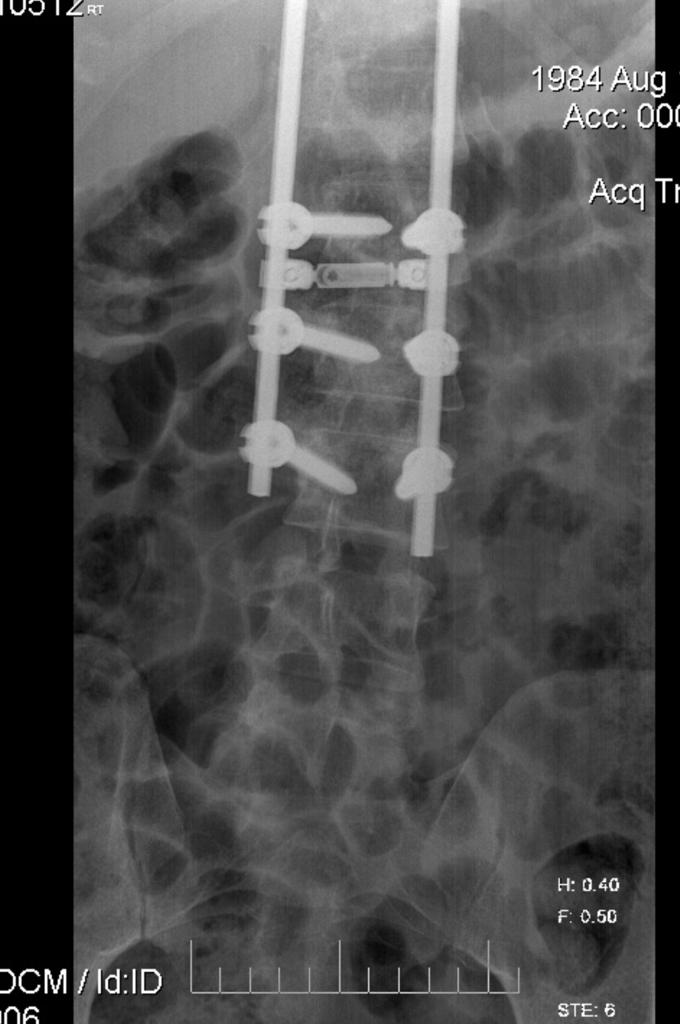

سفاح لندن شالهم لما سوالي العمليه بدون ما يخبرني

مفاجأه جديده بعد مفاجأه إنه مركب لي فقرات صناعيه بدون ما يعطيني خبر أيضاً

بتوصيه من الدكتور الأمريكي الزائر "روس" و الدكتور الشعيبي تم تركيب الجهاز بالكامل بدون مرحله تجريبيه .

وتم تمديد الأسلاك بكامل الظهر بفتحات صغيره من الأعلى وزرع البطاريه والجهاز بالأسفل بدون فتح الظهر بالكامل

الحمدلله .. باقي البرمجه والتجربه

أعتقد من عدد الفريق الموجود وقت العمليه والتصوير إنهم أول مره يسوونها بالطريقه إلي اقترحها الطبيب الامريكي .

إلي بهدلني ان العمليه تمت وانا صاحي ، بنج موضعي + حقن اوكسيكودون على دفعات مع زيادة الالم .